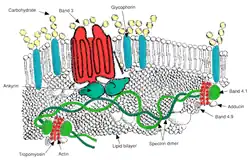

Membrane composition

Red blood cells are deformable, flexible, are able to adhere to other cells, and are able to interface with immune cells. Their membrane plays many roles in this. These functions are highly dependent on the membrane composition. The red blood cell membrane is composed of 3 layers: the glycocalyx on the exterior, which is rich in carbohydrates; the lipid bilayer which contains many transmembrane proteins, besides its lipidic main constituents; and the membrane skeleton, a structural network of proteins located on the inner surface of the lipid bilayer. Half of the membrane mass in human and most mammalian red blood cells are proteins. The other half are lipids, namely phospholipids and cholesterol.[28]

Membrane proteins

The proteins of the membrane skeleton are responsible for the deformability, flexibility and durability of the red blood cell, enabling it to squeeze through capillaries less than half the diameter of the red blood cell (7–8 μm) and recovering the discoid shape as soon as these cells stop receiving compressive forces, in a similar fashion to an object made of rubber.

There are currently more than 50 known membrane proteins, which can exist in a few hundred up to a million copies per red blood cell. Approximately 25 of these membrane proteins carry the various blood group antigens, such as the A, B and Rh antigens, among many others. These membrane proteins can perform a wide diversity of functions, such as transporting ions and molecules across the red cell membrane, adhesion and interaction with other cells such as endothelial cells, as signaling receptors, as well as other currently unknown functions. The blood types of humans are due to variations in surface glycoproteins of red blood cells. Disorders of the proteins in these membranes are associated with many disorders, such as hereditary spherocytosis, hereditary elliptocytosis, hereditary stomatocytosis, and paroxysmal nocturnal hemoglobinuria.[28][29]

The red blood cell membrane proteins organized according to their function:

Transport

- Band 3 – Anion transporter, also an important structural component of the red blood cell membrane, makes up to 25% of the cell membrane surface, each red cell contains approximately one million copies. Defines the Diego Blood Group;[32]

- Aquaporin 1 – water transporter, defines the Colton Blood Group;

- Glut1 – glucose and L-dehydroascorbic acid transporter;

- MCT1 – Monocarboxylate transporter for exporting Lactic acid to the liver. See Cori cycle.;[33]

- Kidd antigen protein – urea transporter;

- RHAG – gas transporter, probably of carbon dioxide, defines Rh Blood Group and the associated unusual blood group phenotype Rhnull;

- Na+/K+ – ATPase;

- Ca2+ – ATPase;

- Na+ K+ 2Cl− – cotransporter;

- Na+-Cl− – cotransporter;

- Na-H exchanger;

- K-Cl – cotransporter;

- Gardos Channel.

Cell adhesion

- ICAM-4 – interacts with integrins;

- BCAM – a glycoprotein that defines the Lutheran blood group and also known as Lu or laminin-binding protein.

Structural role – The following membrane proteins establish linkages with skeletal proteins and may play an important role in regulating cohesion between the lipid bilayer and membrane skeleton, likely enabling the red cell to maintain its favorable membrane surface area by preventing the membrane from collapsing (vesiculating).

- Ankyrin-based macromolecular complex – proteins linking the bilayer to the membrane skeleton through the interaction of their cytoplasmic domains with Ankyrin.

- Band 3 – also assembles various glycolytic enzymes, the presumptive CO2 transporter, and carbonic anhydrase into a macromolecular complex termed a "metabolon", which may play a key role in regulating red cell metabolism and ion and gas transport function.

- RHAG – also involved in transport, defines associated unusual blood group phenotype Rhmod.

- Protein 4.1R-based macromolecular complex – proteins interacting with Protein 4.1R.

- Protein 4.1R – weak expression of Gerbich antigens;

- Glycophorin C and D – glycoprotein, defines Gerbich Blood Group;

- XK – defines the Kell Blood Group and the Mcleod unusual phenotype (lack of Kx antigen and greatly reduced expression of Kell antigens);

- RhD/RhCE – defines Rh Blood Group and the associated unusual blood group phenotype Rhnull;

- Duffy protein – has been proposed to be associated with chemokine clearance;[34]

- Adducin – interaction with band 3;

- Dematin- interaction with the Glut1 glucose transporter.